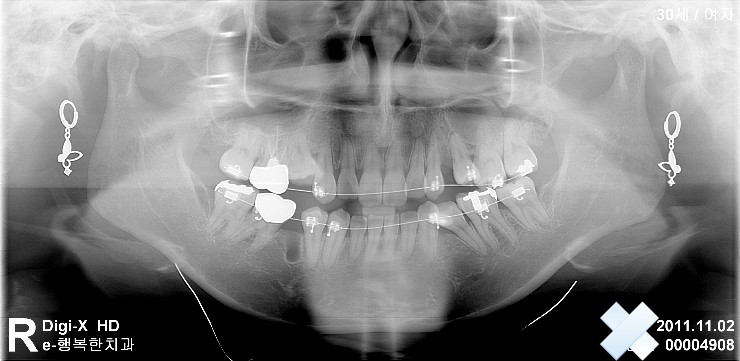

아래 사진은 제가 근무하는 병원에서 찍은 사진 입니다.

첫 사진은 교정후 3-4개월 정도 지난 후 이구요

그리고 2번째 사진은 최근 3월에 찍은사진 입니다.

네.... 걱정이 많이 되겠군요. 제가 실제치아를 진단한 것은 아니라 정확하게 말씀드리긴 힘들지만 사진 상으로는 크게 문제 있어 보이진 않은 것 같습니다. 보통 교정치료 하고나면 개인 마다 차이가 있겠지만 작은 어금니가 많이 흔들리는 편이지요. 유지과정을 잘 보내고 나면 괜찮아 질것 같으니 넘 걱정 마시기 바랍니다.